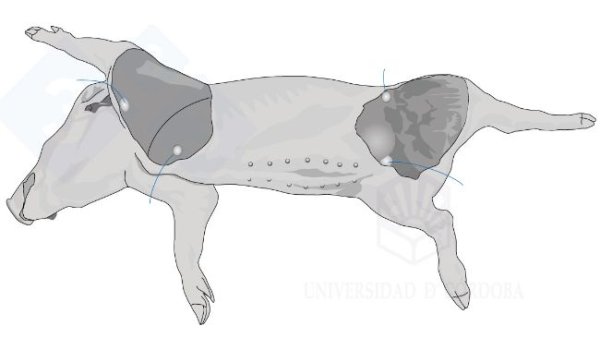

Necropsy manual: Necropsy of a piglet in lateral decubitus (I)

This new section, coordinated by the pathological anatomy team of the University of Cordoba, Spain, will show us, in a very visual and practical way, how to perform a necropsy on a pig.

This new section, coordinated by the pathological anatomy team of the University of Cordoba, Spain, will show us, in a very visual and practical way, how to perform a necropsy on a pig.

In the first two installments, we covered necropsy in lateral decubitus. In this third installment, we will look at necropsy in the supine position

In this second installment, we cover extracting the tongue, trachea, lungs, and heart in one piece. We will extract the organs of the abdominal cavity, both the digestive system and the urinary and genital tracts. In the head, we will access the nasal turbinates, brain, and cerebellum.